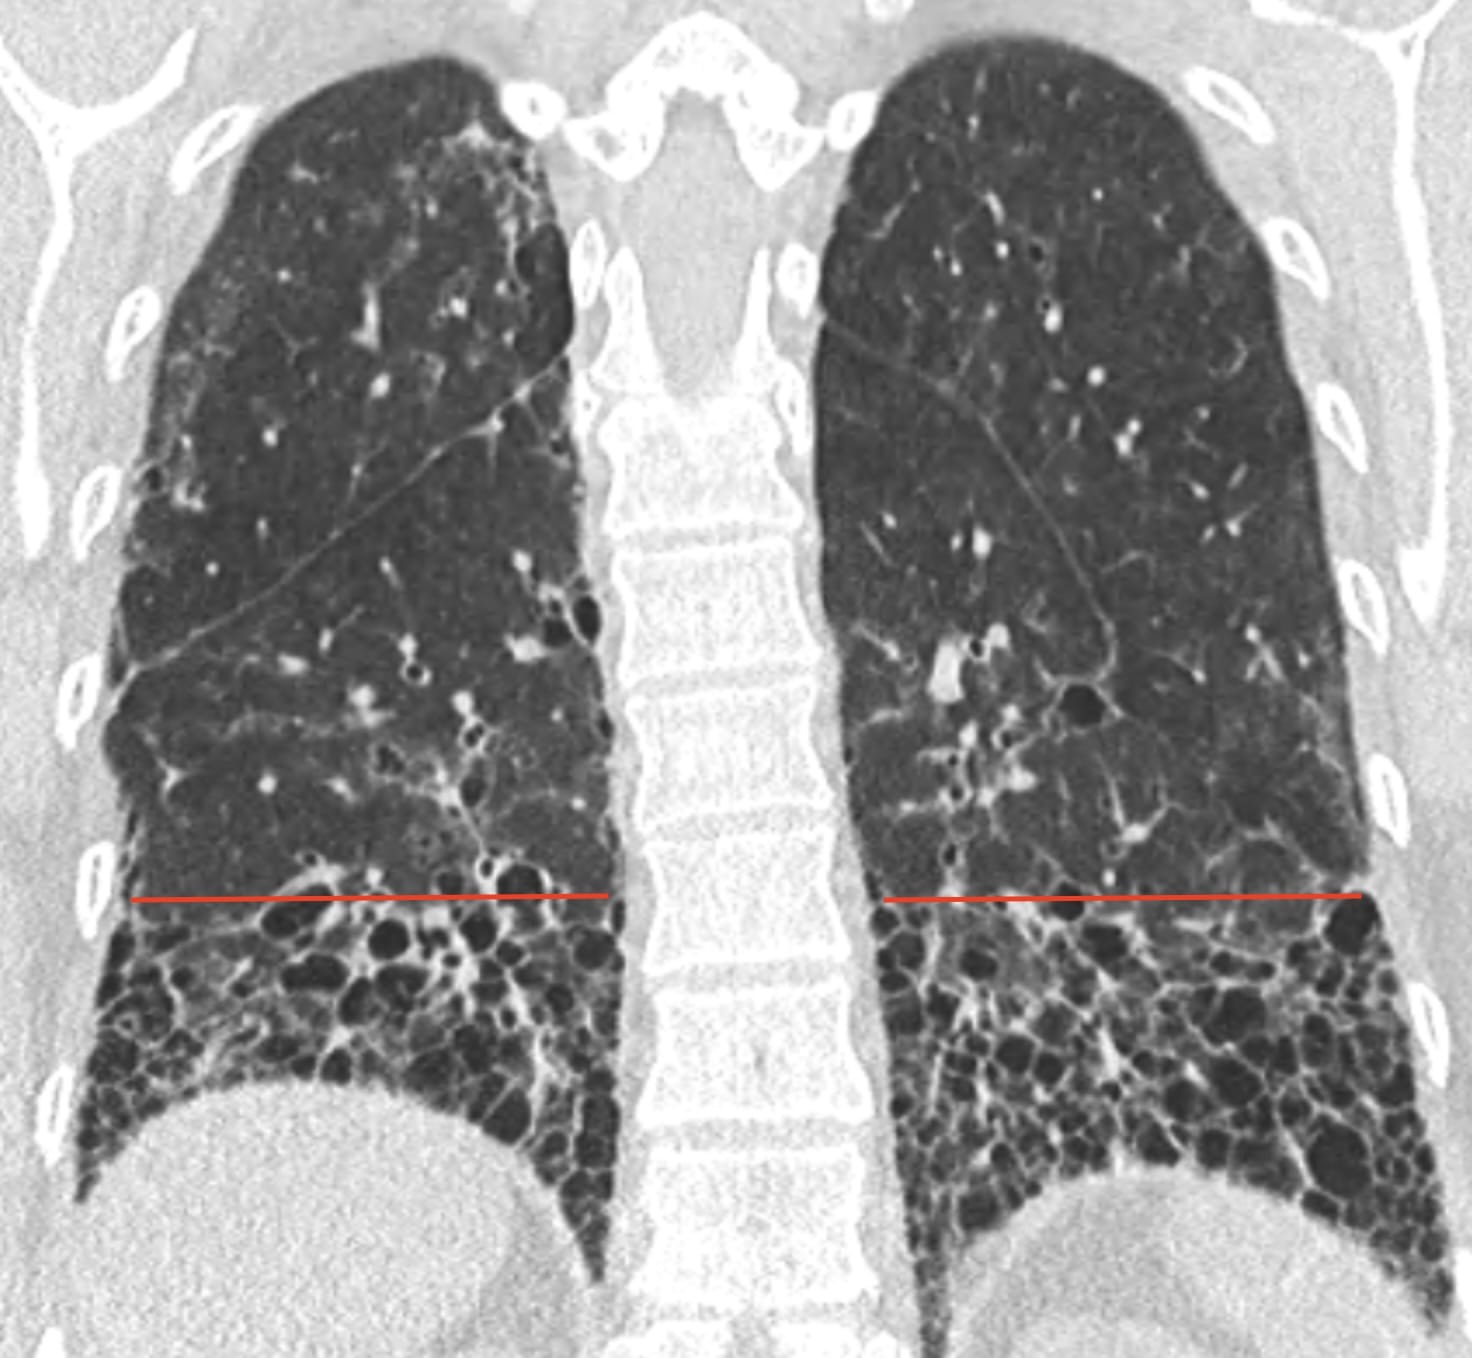

- Usual Interstitial Pneumonia